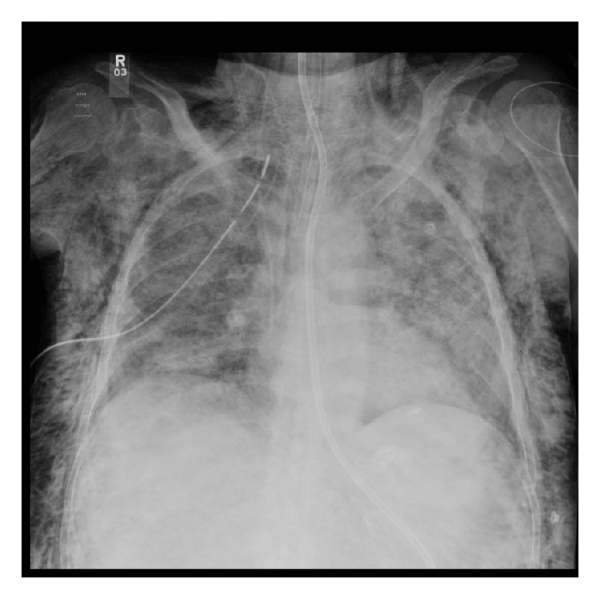

After NG tube insertion, chest X-ray showed misplaced NG tube at the right main bronchus down to the right pleural space and development of new 7.8 mm right sided pneumothorax (Figure 1, chest X-ray). The NG tube had been immediately removed and PEEP was decreased to 5 cmH2O. Over few minutes, the patient became progressively hypotensive and hypoxic, requiring higher doses of norepinephrine infusion and FiO2 of 60% to maintain 95% saturation. Right sided chest tube was inserted and the repeated X-ray revealed new subcutaneous emphysema (Figure 2). Using direct laryngoscopy technique, nasogastric tube was inserted under vision.